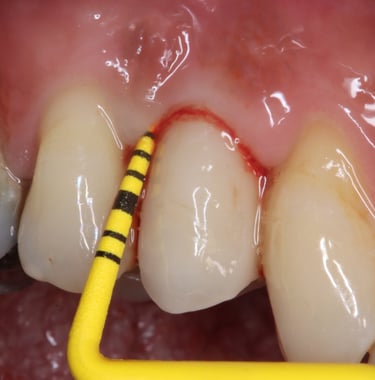

Parodontologie pour l'omnipraticien

Diagnostic et traitement